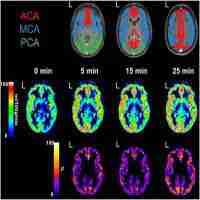

Noninvasive magnetic resonance imaging evaluation of cerebral blood flow with acetazolamide challenge in patients with cerebrovascular stenosis

| Subject Keyword | Journal: Journal of Magnetic Resonance Imaging (JMRI) Cerebral Blood Flow Cerebrovascular Disease Magnetic Resonance Imaging |